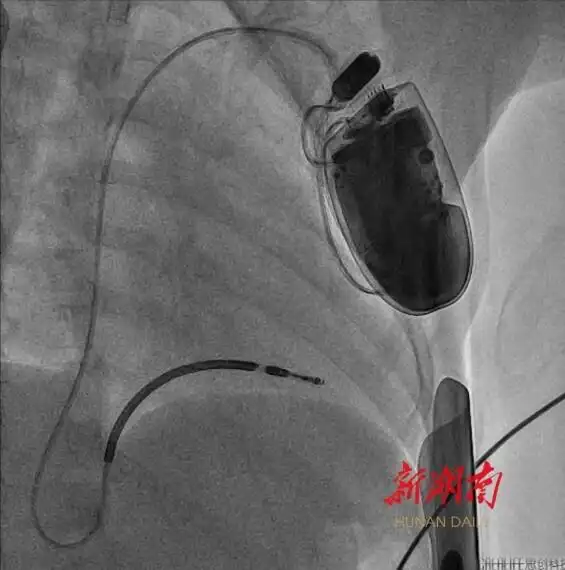

湖南日報4月22日訊(文字/視頻 全媒體記者 周陽樂 通訊員 黃娟 宋青青)今天,記者從湖南省兒童醫(yī)院獲悉,該院血管內(nèi)科陳智主任團隊近期成功為一名年僅4歲半、體重16公斤的短QT間期綜合征患兒植入心臟轉(zhuǎn)復(fù)律自動除顫器(ICD)。此為中南地區(qū)年齡最小、體重最低的兒童心臟轉(zhuǎn)復(fù)律自動除顫器手術(shù)案例。

體重輕、血管細(xì)小、皮下脂肪薄……術(shù)前,團隊對手術(shù)路徑設(shè)計、導(dǎo)管操作方式、麻醉方案及術(shù)中突發(fā)狀況處理等細(xì)節(jié)進(jìn)行了嚴(yán)密論證。4月16日上午,在麻醉師全程監(jiān)護(hù)下,團隊結(jié)合血管超聲的特點,成功經(jīng)腋靜脈,將電極導(dǎo)線精準(zhǔn)送達(dá)右心室心尖部,并通過調(diào)整預(yù)留適合孩子生長的長度,經(jīng)程控測試確認(rèn)最佳起搏閾值后,與ICD裝置完成精準(zhǔn)連接。

經(jīng)過2個小時的努力,手術(shù)順利結(jié)束。術(shù)后,護(hù)理團隊為悅悅制定了個性化護(hù)理方案,重點防控感染、導(dǎo)線移位等風(fēng)險,通過多學(xué)科協(xié)作保障醫(yī)療安全。目前,悅悅恢復(fù)狀況良好,未再出現(xiàn)室顫發(fā)作。